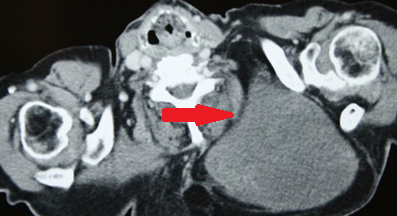

Μωβ βέλη: λιπώματα. Καφέ βέλος: αδενοκαρκίνωμα σμηγματώδους αδένα (Ευγενική παραχώρηση Dr. V. Penopoulos)